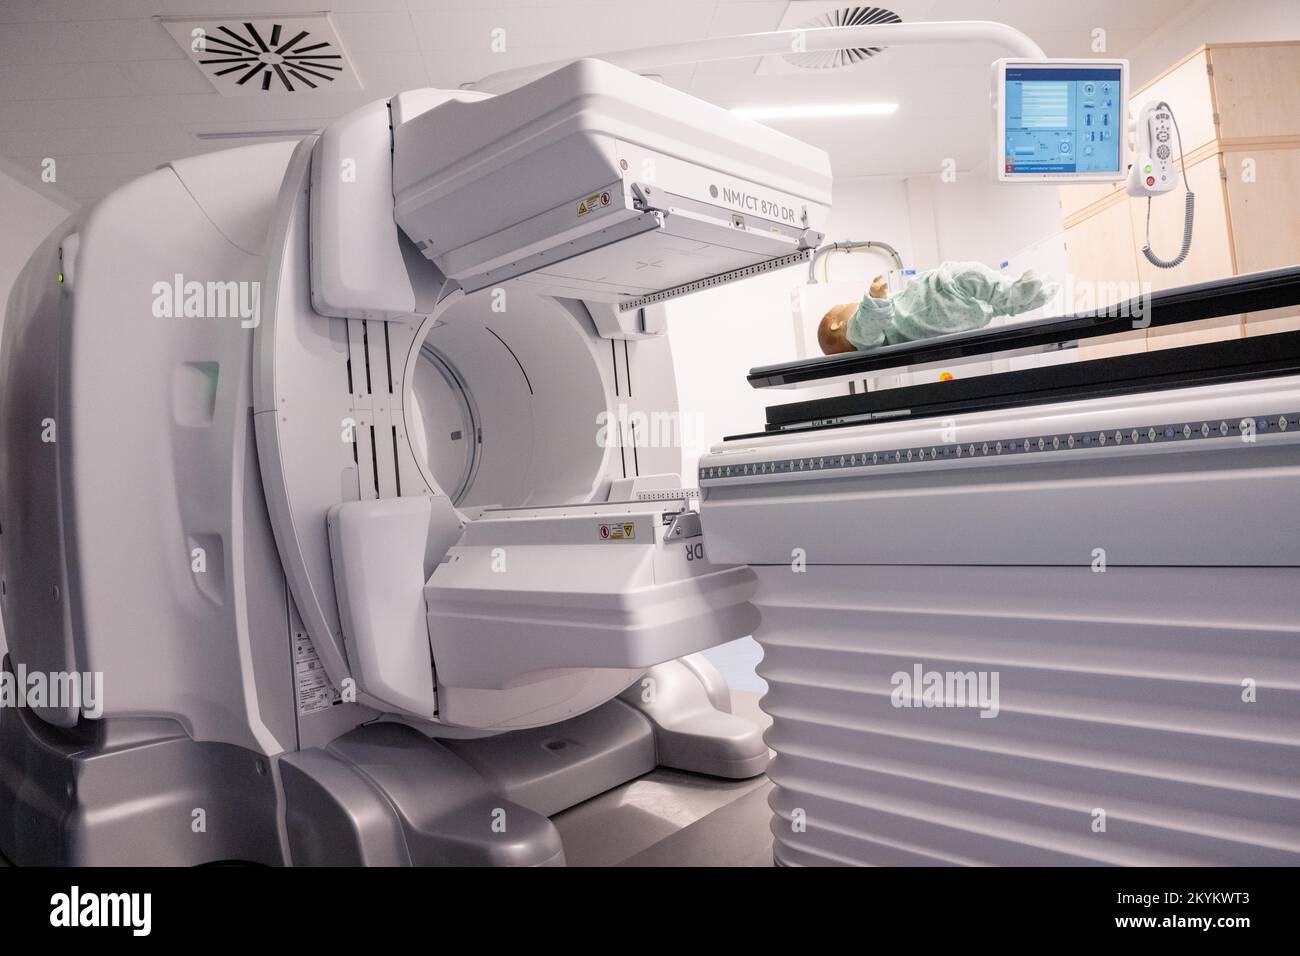

RM2KYKWT3–01 décembre 2022, Mecklembourg-Poméranie occidentale, Greifswald: Une unité NM/CT 870 DR de General Electric Medical Systems, Israël est sur le point d'être remise dans les salles de la clinique pédiatrique du centre médical de l'université Greifswald. Ce système SPECT/CT permet des examens médicaux nucléaires encore plus précis. Ceci est nécessaire pour les options de traitement spéciales telles que la thérapie par radio-isotope. La tomodensitométrie (CT) utilise un grand nombre d'images radiologiques pour calculer les images numériques. Une acquisition SPECT, en revanche, utilise une caméra gamma pour rendre visible le faible rayonnement des médicaments radioactifs. Dans cette wa

RM2KYKWRY–01 décembre 2022, Mecklembourg-Poméranie occidentale, Greifswald: Une unité NM/CT 870 DR de General Electric Medical Systems, Israël est sur le point d'être remise dans les salles de la clinique pédiatrique du centre médical de l'université Greifswald. Ce système SPECT/CT permet des examens médicaux nucléaires encore plus précis. Ceci est nécessaire pour les options de traitement spéciales telles que la thérapie par radio-isotope. La tomodensitométrie (CT) utilise un grand nombre d'images radiologiques pour calculer les images numériques. Une acquisition SPECT, en revanche, utilise une caméra gamma pour rendre visible le faible rayonnement des médicaments radioactifs. Dans cette wa

RM2KYKWRC–01 décembre 2022, Mecklembourg-Poméranie occidentale, Greifswald: Une unité NM/CT 870 DR de General Electric Medical Systems, Israël est sur le point d'être remise dans les salles de la clinique pédiatrique du centre médical de l'université Greifswald. Ce système SPECT/CT permet des examens médicaux nucléaires encore plus précis. Ceci est nécessaire pour les options de traitement spéciales telles que la thérapie par radio-isotope. La tomodensitométrie (CT) utilise un grand nombre d'images radiologiques pour calculer les images numériques. Une acquisition SPECT, en revanche, utilise une caméra gamma pour rendre visible le faible rayonnement des médicaments radioactifs. Dans cette wa

RM2KYM017–01 décembre 2022, Mecklembourg-Poméranie occidentale, Greifswald: Un dispositif NM/CT 870 DR de General Electric Medical Systems, Israël est sur le point d'être remis dans les salles de la clinique pédiatrique du centre médical de l'université de Greifswald. Ce système SPECT/CT permet des examens médicaux nucléaires encore plus précis. Ceci est nécessaire pour les options de traitement spéciales telles que la thérapie par radio-isotope. La tomodensitométrie (CT) utilise un grand nombre d'images radiologiques pour calculer les images numériques. Une acquisition SPECT, en revanche, utilise une caméra gamma pour rendre visible le faible rayonnement des médicaments radioactifs. Dans cette

RM2KYM01N–01 décembre 2022, Mecklembourg-Poméranie occidentale, Greifswald: Une unité NM/CT 870 DR de General Electric Medical Systems, Israël est sur le point d'être remise dans les salles de la clinique pédiatrique du centre médical de l'université Greifswald. Ce système SPECT/CT permet des examens médicaux nucléaires encore plus précis. Ceci est nécessaire pour les options de traitement spéciales telles que la thérapie par radio-isotope. La tomodensitométrie (CT) utilise un grand nombre d'images radiologiques pour calculer les images numériques. Une acquisition SPECT, en revanche, utilise une caméra gamma pour rendre visible le faible rayonnement des médicaments radioactifs. Dans cette wa

RM2KYKWW0–01 décembre 2022, Mecklembourg-Poméranie occidentale, Greifswald: Une unité NM/CT 870 DR de General Electric Medical Systems, Israël est sur le point d'être remise dans les salles de la clinique pédiatrique du centre médical de l'université Greifswald. Ce système SPECT/CT permet des examens médicaux nucléaires encore plus précis. Ceci est nécessaire pour les options de traitement spéciales telles que la thérapie par radio-isotope. La tomodensitométrie (CT) utilise un grand nombre d'images radiologiques pour calculer les images numériques. Une acquisition SPECT, en revanche, utilise une caméra gamma pour rendre visible le faible rayonnement des médicaments radioactifs. Dans cette wa

RM2KYM01C–01 décembre 2022, Mecklembourg-Poméranie occidentale, Greifswald: Une unité NM/CT 870 DR de General Electric Medical Systems, Israël est sur le point d'être remise dans les salles de la clinique pédiatrique du centre médical de l'université Greifswald. Ce système SPECT/CT permet des examens médicaux nucléaires encore plus précis. Ceci est nécessaire pour les options de traitement spéciales telles que la thérapie par radio-isotope. La tomodensitométrie (CT) utilise un grand nombre d'images radiologiques pour calculer les images numériques. Une acquisition SPECT, en revanche, utilise une caméra gamma pour rendre visible le faible rayonnement des médicaments radioactifs. Dans cette wa

RM2KYM01E–01 décembre 2022, Mecklembourg-Poméranie occidentale, Greifswald: Une unité NM/CT 870 DR de General Electric Medical Systems, Israël est sur le point d'être remise dans les salles de la clinique pédiatrique du centre médical de l'université Greifswald. Ce système SPECT/CT permet des examens médicaux nucléaires encore plus précis. Ceci est nécessaire pour les options de traitement spéciales telles que la thérapie par radio-isotope. La tomodensitométrie (CT) utilise un grand nombre d'images radiologiques pour calculer les images numériques. Une acquisition SPECT, en revanche, utilise une caméra gamma pour rendre visible le faible rayonnement des médicaments radioactifs. Dans cette wa